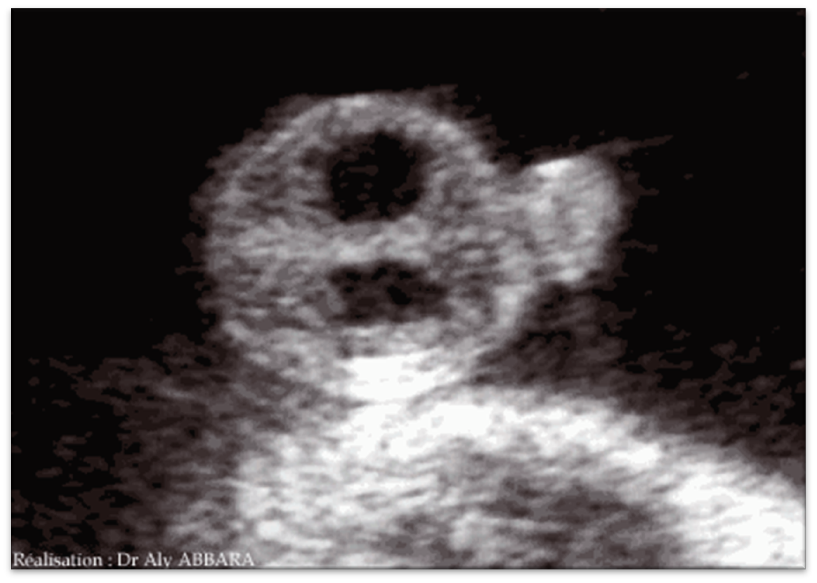

Hydronephrosis - UPJ Obstruction

Hydronephrosis